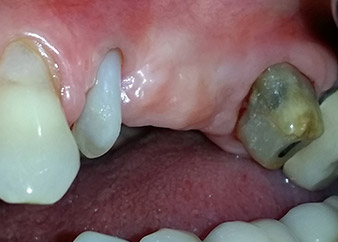

Une patiente de 58 ans se plaignait de douleurs et d'une mobilité accrue de la dent pilier 24 de son bridge. Présence d'une inflammation parodontale avec formation de poches de 7 mm de profondeur dans le sens mésiobuccal et de plus de 12 mm dans le sens distal, ainsi que d'une atteinte de la furcation au troisième degré. La radiographie a par ailleurs révélé une lésion parodontale étendue autour de la région apicale de la dent 24 ayant préalablement reçu un traitement endodontique (alio loco) (Fig. 1).

Un an plus tôt, les dents 25 et 26 avaient été extraites à la suite d'un traumatisme et pour cause d'atteinte endo-parodontale, avant la pose du bridge. Une lésion endo-parodontale combinée a été diagnostiquée pour la dent 24, d'étiologie incertaine. La patiente voulait conserver ses dents piliers 24 et 27 et refusait toute prothèse amovible à titre définitif, et même provisoire. Par conséquent, malgré un pronostic défavorable compte tenu des résultats des radios et des examens cliniques, il a été convenu de faire le maximum pour conserver les deux dents.